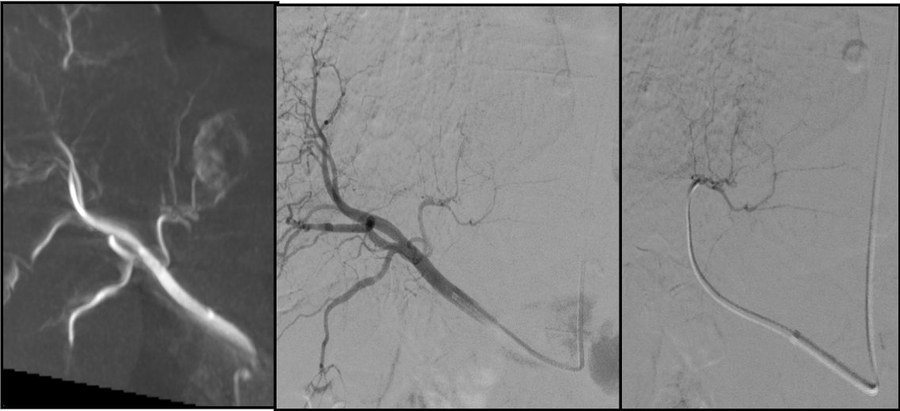

🎯Peripheral vascular radiology

Angioplasty, stenting, renal artery interventions.

💉Venous recanalisation

Iliac and vena caval stenting. Post-thrombotic syndrome.